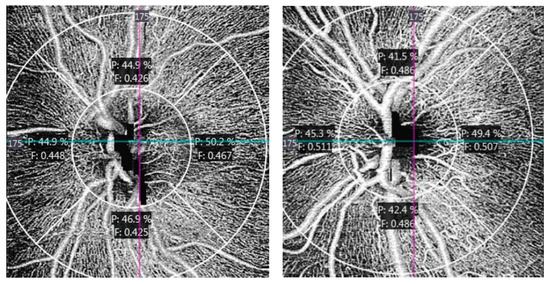

3. Results